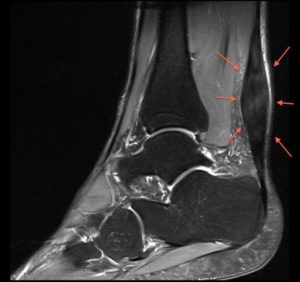

Εικόνα 2 : Τενοντοπάθεια αχιλλείου στο μέσαιο τμήμα του . Διαθέσιμη στον διαδικτυακό ιστότοπο(https://www.google.gr/search?q=%CF%84%CE%B5%CE%BD%CE%BF%CE%BD%CF%84%CE%BF%CF%80%CE%B1%CE%B8%CE%B5%CE%B9%CE%B1+%CE%B1%CF%87%CE%B9%CE%BB%CE%BB%CE%B5%CE%B9%CE%BF%CF%85+%CF%84%CE%B5%CE%BD%CE%BF%CE%BD%CF%84%CE%B1&source=lnms&tbm=isch&sa=X&ved=0ahUKEwiS0LmbyfbeAhXFfFAKHUo6BpEQ_AUIDigB&biw=1252&bih=582#imgrc=_) , (26/11/2018)

-Η τενοντοπάθεια του αχιλλείου μπορεί να υπάρχει στην ένθεση ή στο μέσο του τμήμα. Περισσότερο συχνά εντοπίζεται στο μέσο του τένοντα, 2-6 εκατοστά από την πτέρνα, που είναι και το σημείο με την φτωχότερη αιμάτωση (55-65% των περιπτώσεων) και λιγότερο συχνά στο κάτω άκρο του τένοντα στο σημείο που συνδέεται με την πτέρνα (20-25% των περιπτώσεων).